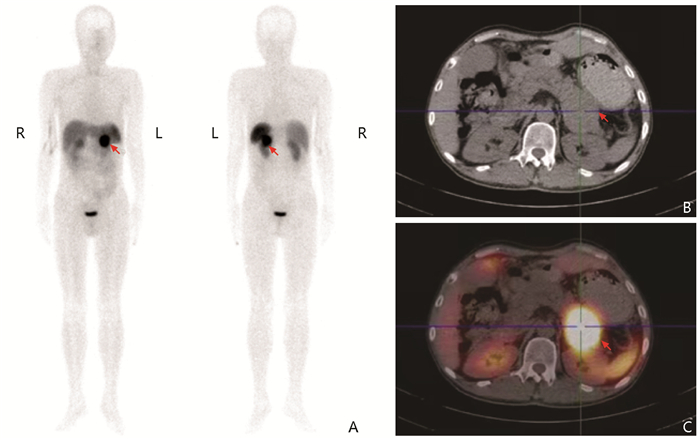

肿瘤性骨软化症68Ga-DOTATATE PET/CT显像特点分析

张雨薇, 景红丽

2023, 2(3): 398-405. DOI: 10.12376/j.issn.2097-0501.2023.03.010